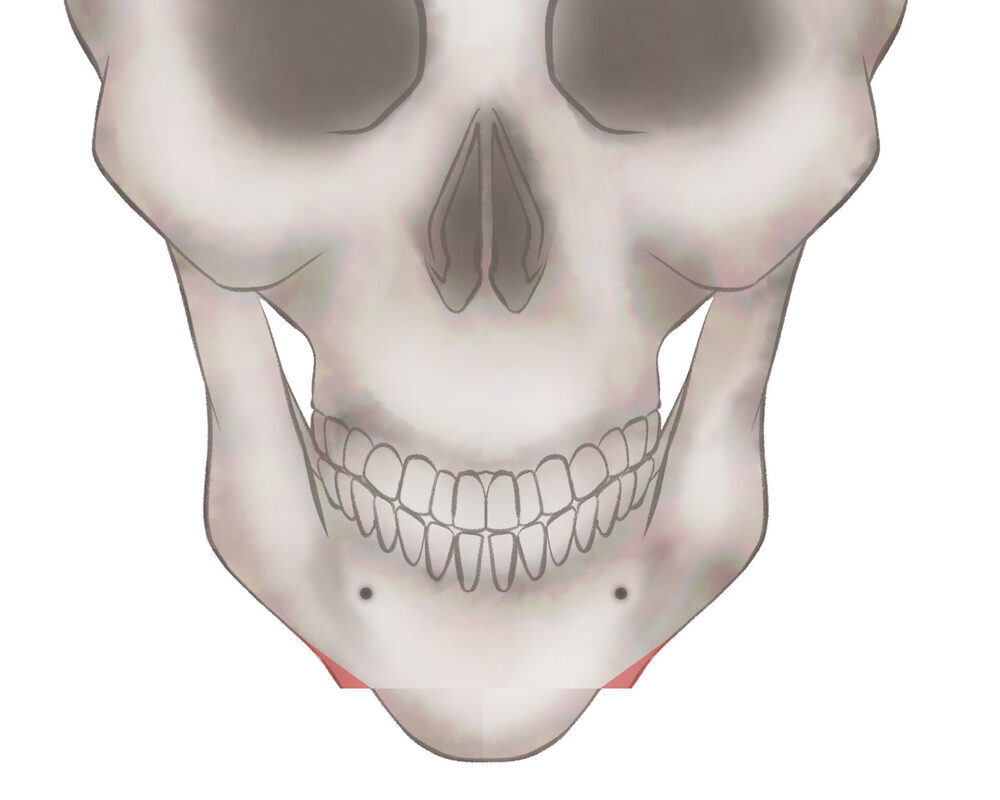

オトガイ骨切り(中抜き)

1.切開線をデザインします

2.骨を切除します

3.骨を移動させ段差を削ります

4.プレートで固定します